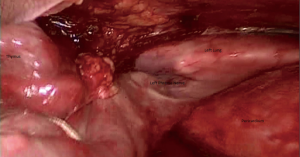

The 30° is introduced and the hemithorax is evaluated. The right phrenic nerve is defined with its relations to thymus or a thymoma VSports app下载. We begin the dissection with resection of the right sided pericardiophrenic fatty tissue. Then the dissection of the thymus begins by removing it from the pericardium anterior to the phrenic nerve with blunt dissection or with LigaSure™ 5 mm tissue sealer (Medtronic, Inc. , Doral, FL) (Figures 3,4).

Then the thymus is dissected of the sternum by opening the mediastinal pleura along the right internal mammary artery/vein under the sternum (Figure 5). The dissection from the right side parallel to the phrenic nerve enables visualization of the superior vena cava and junction of both innominate veins clearly becomes visible V体育官网. The most dangerous and accident inviting part of this operation is the dissection of the upper poles. By gentle traction on both superior poles of the thymus could be dissected and under direct visualisation (Figure 6). The superior poles dissection is best provided with gentle force applied caudally, with the use of countertraction dissection towards thyroid gland. The arterial and venous branches from the internal mammary vessels could be identified and clipped. The major thymic veins may be at different numbers and locations could be dissected and divided by clipping (Figures 7,8).